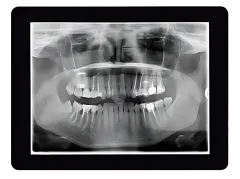

Digital Imaging

Digital imaging is a cornerstone of modern orthodontic care at White Brown Smiles. By utilizing advanced imaging technology, we’re able to get a comprehensive view of your teeth, jaw, and facial structure, ensuring a precise diagnosis and customized treatment plan.

- Detailed Diagnosis — High-resolution digital images reveal even the smallest details, helping us identify potential issues early.

- Minimized Radiation — Digital imaging uses significantly less radiation than traditional X-rays, ensuring a safer experience for patients of all ages.

- Improved Communication — Digital images allow us to clearly explain your orthodontic needs and show you the areas we’ll be addressing.

Digital imaging ensures we have all the information we need to provide you with the highest standard of care, setting the stage for exceptional results.